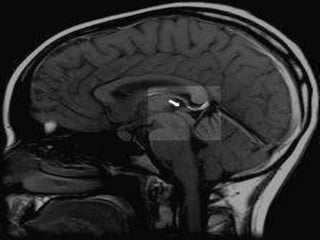

EPIPHYSIS (PINEAL GLAND)

Stained with haematoxylin and eosin

1 - pinealocytes

2- pineal sand (salts of calcium,

magnesium and silicon

 Calcification of PinealGland

 Calcification of the pineal gland is typical in

young adults, and has been observed in

children as young as two years of age.The

internal secretions of the pineal gland inhibit

the development of the reproductive glands

because when it is severely damaged in

children, development of the sexual organs

and the skeleton are accelerated.